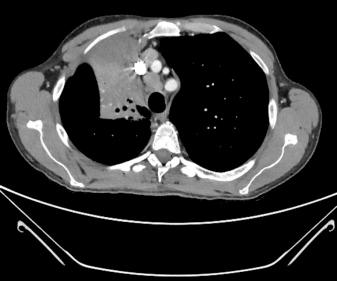

Other than a chest radiograph, patients will have had a CT scan of their thorax to demonstrate radiological evidence of size, number and location of a tumour either in the right lung or the left lung. In addition, there may be mediastinal lymphadenopathy ( Fig. 41.3 ). Before lung resection, a separate general anaesthetic for lung biopsy and cervical mediastinoscopy is often required for diagnosis and staging of suspected lung cancer.

Fig. 41.3, Computed tomographic scan showing mediastinal lymphadenopathy in the pretracheal area and obstruction of the right upper lobe bronchus.